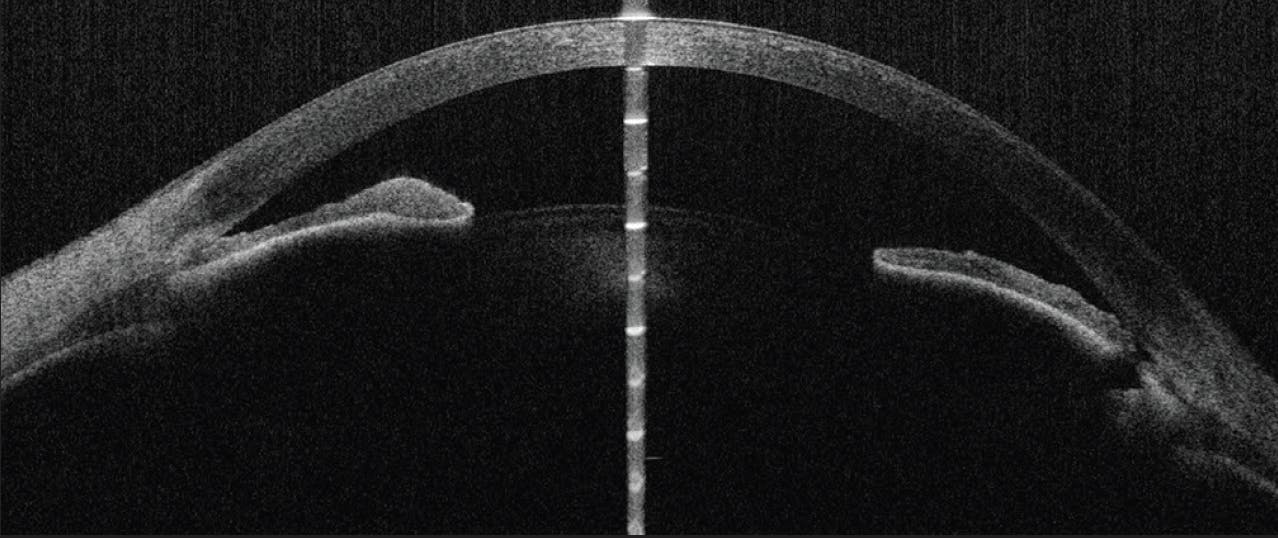

One month after the LPIs, the patient’s unmedicated IOP is 12 mm Hg OU. In the left eye, the pupil has a diameter of 3 mm, and its response to light is sluggish. Two months after the LPIs, the patient presents with an IOP of 43 mm Hg OS. The iridotomy has been blocked by iridocorneal contact with some recurrence of pupillary block but no frank iris bombe (Figure 5). Repeat testing confirms visual field loss in the left eye. Therapy with acetazolamide and four classes of topical ocular hypotensive medication is initiated but fails to reduce the IOP. An urgent lensectomy is therefore performed.

Figure 5. AS-OCT imaging of the left eye shows blockage of the LPI by iridocorneal contact and a recurrence of pupillary block.

Understanding the mechanisms for the angle closure might facilitate a decision on how to proceed. The anterior segment OCT (AS-OCT) images obtained before lens extraction show an exaggerated lens vault (“volcano”) configuration (Figures 4 and 5). In Figure 4, the angles appear to be closed or very narrow despite a patent iridotomy. Plateau configuration is likely also a contributing factor, especially given the patient’s age. Ultrasound biomicroscopy (UBM) could help identify additional etiologies such as plateau iris syndrome that AS-OCT imaging may not be able to detect definitively. Other anatomic causes that can be assessed by UBM include ciliary effusions, iridociliary cysts or tumors, and ciliary block.